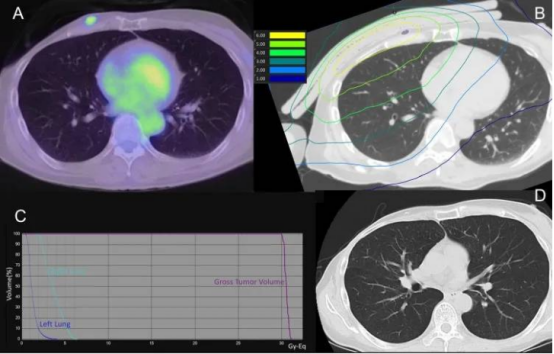

另一位61岁的患者,因多次复发、传统治疗手段用尽,在BNCT治疗后90天的随访中,CT显示肿瘤内部形成空洞,体积大幅缩小,且未出现放射性肺炎等副作用。

(A)硼中子俘获疗法(BNCT)肺部剂量分布图(紫色区域代表肿瘤大体靶区GTV);(B)治疗后90天的CT影像(未显示放射性肺炎迹象,且肿瘤大体靶区GTV缩小)